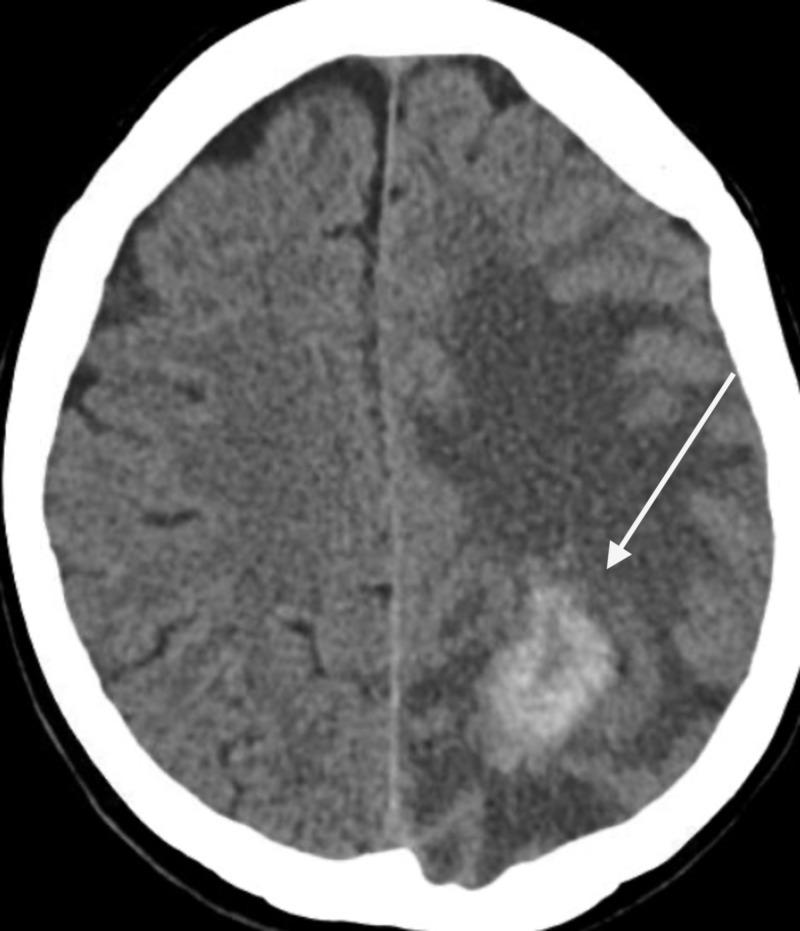

Cerebral amyloidoma is a rare form of amyloidosis with a localized tumor like an amyloid deposition in the brain composed of insoluble fibrillary protein with cross beta-sheet conformation. Its usual presentation includes vision loss, seizures, behavioral changes, cognitive decline, and recurrent headaches. It has a benign course with a slow progression, and it is not associated with dissemination. We report a case of a 65-year-old Caucasian woman who presented with symptoms of progressively worsening cognitive dysfunction of six months' duration. From CT of the brain, it was found that she had a right frontal and left parietal hemorrhagic mass with a large amount of vasogenic edema and a midline shift. MRI showed heterogeneously enhancing hemorrhagic mass of 5.2 cm x 2.6 cm x 3.6 cm in size, with a satellite lesion. Initially, this was suspected to be a high-grade glioma vs. metastatic hemorrhagic lesions. She underwent stereotactic biopsy of the mass, and histopathology was consistent with cerebral amyloidoma with marked IgA lambda plasma cell differentiation. She did not have any evidence of systemic amyloidosis, and therefore, she is being clinically observed with a regular follow-up and annual CT surveillance. She has remained stable over the past two years, although she has residual cognitive dysfunction. Cerebral amyloidoma can mimic malignant central nervous system (CNS) neoplasms and should be considered as a differential of any single or multiple mass lesions occurring in the white matter region of the brain with a characteristic appearance of "hyperdense lesions" on CT. It is a benign disease with no metastatic potential that usually resolves entirely after resection.